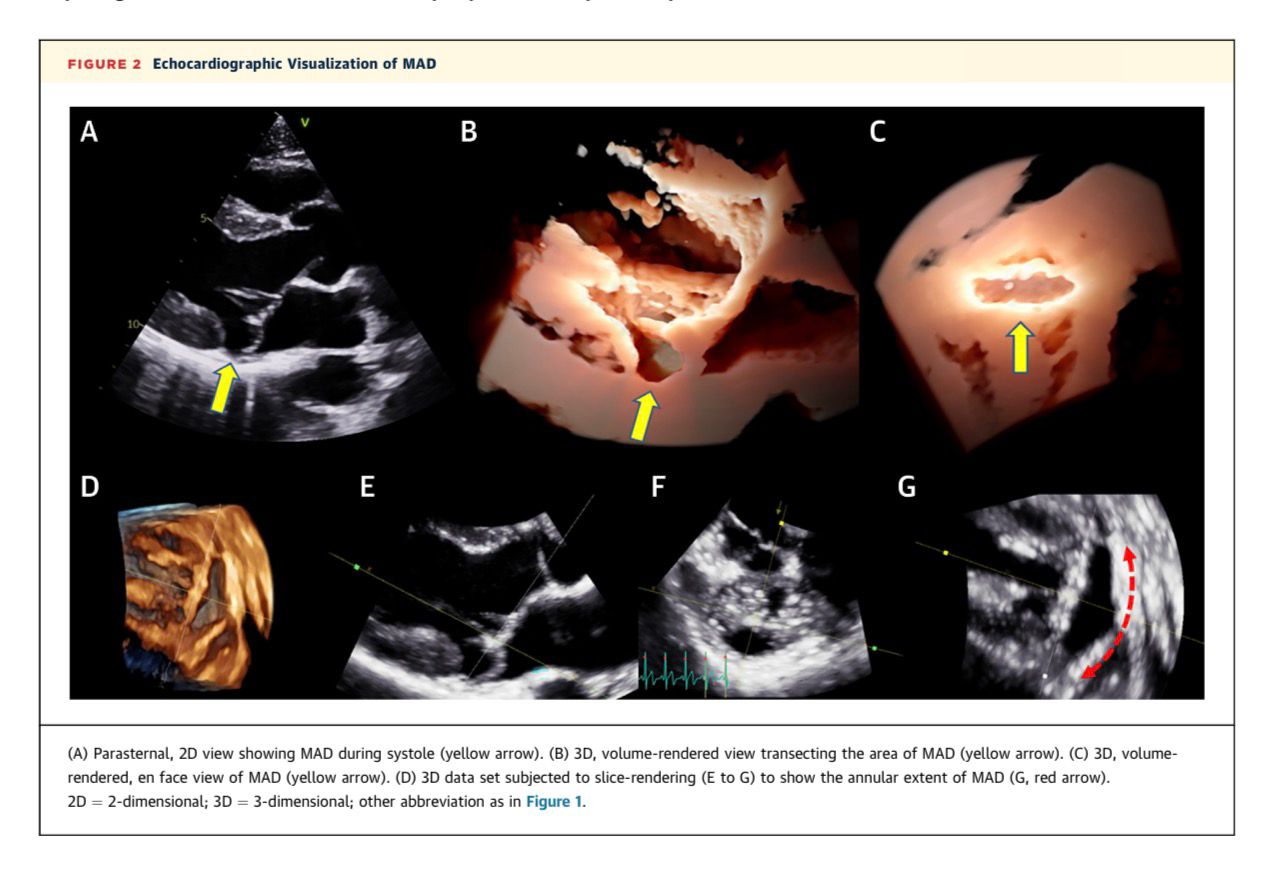

Mitral Qapaq Prolapsı Fonunda Mitral Anulyar Ayrılma

Mitral anulyar  dislokasiya (Mitral Annular Disjunction, MAD), sol atrium/mitral qapaq anulusu ilə sol mədəciyin miokardı arasında yaranan ayrılma kimi xarakterizə olunur və aritmiyalı mitral qapaq prolapsı olan xəstələrdə tez-tez müşahidə edilir.